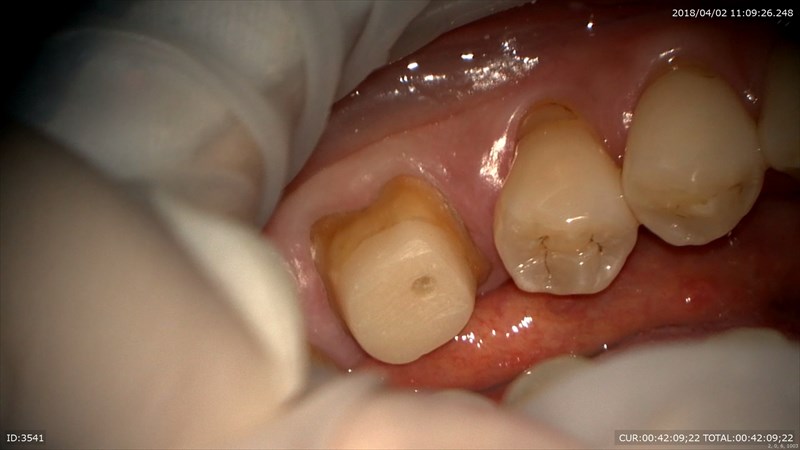

担当している技工士間中さんは妥協を許さない人。だから良い仕事が出来る。何回でも突き返してきます。笑。特に難しいのはこの歯茎と歯の境目をしっかり出すこと。歯茎の厚みなどを考慮して糸を変えます。

だからこのように1本糸を差し込み

痛くない様にするにはマイクロスコープを使用します。